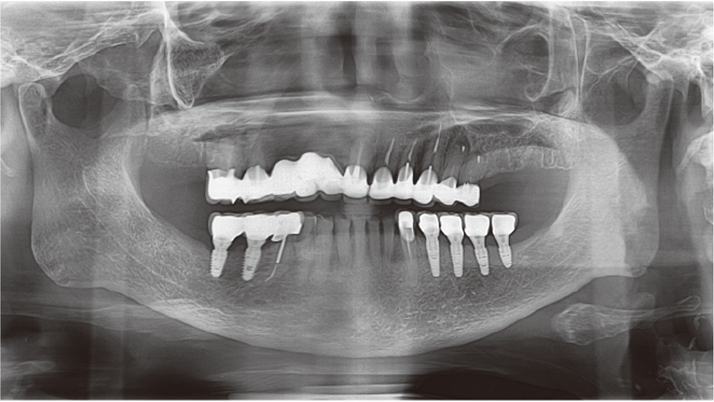

Clinical case: # 46 implant placement & GBR using i-Gen membrane for significant vertical resorption & mixed bone defect

- Courtesy of Dr. Iulian Filipov, Romania -

AnyRidge, mandibular posterior, i-Gen, resorption, bone defect, bone regeneration, space management, #46, GBR, Dr. Iulian Filipov

AnyRidge implant system, i-Gen

“AnyRidge KnifeThread achieves excellent stability in regenerated bone & even in only 3mm bone height!”